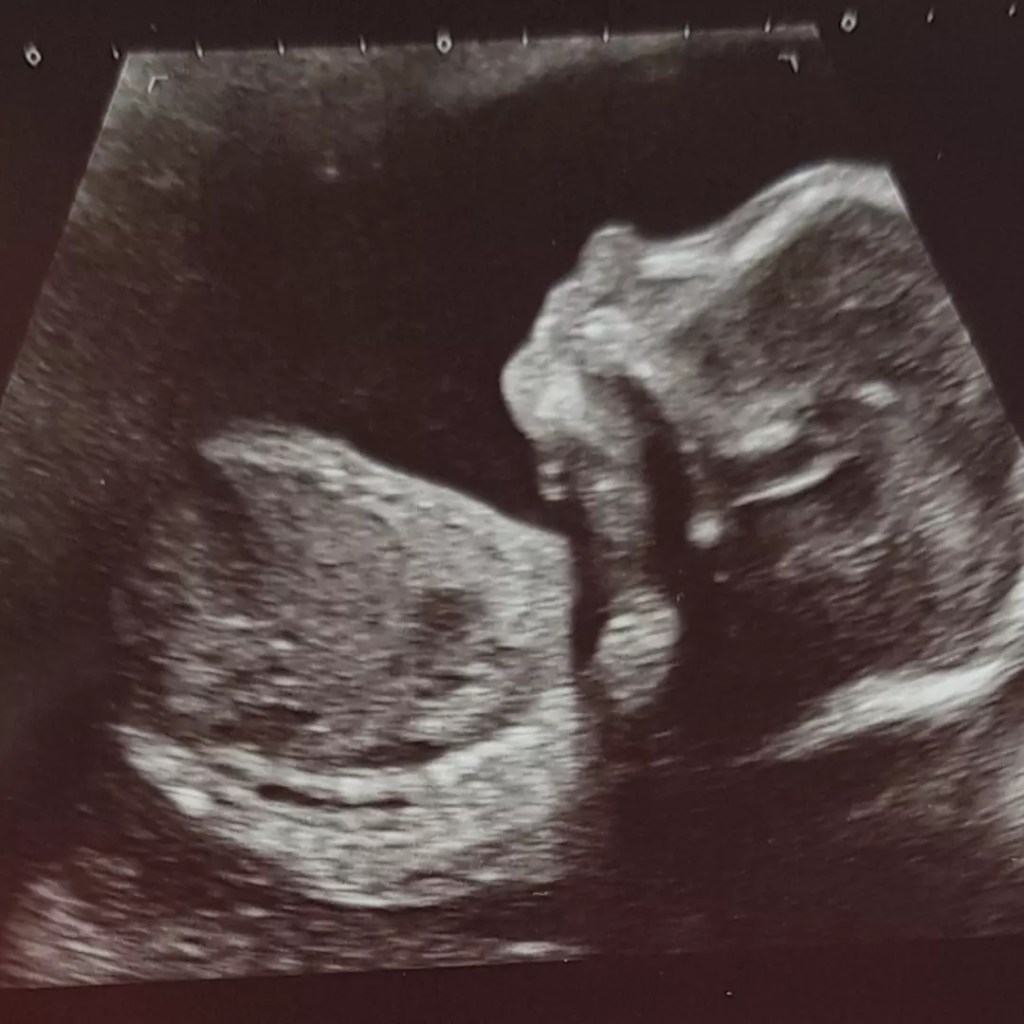

Can you believe I am now 22 weeks! That is INSANE! Since I last wrote we have had another couple of scans. 20 week scan gave me a glimpse of what I am in store for… there is no doubt this baby is mine! Lazy and stubborn! He/she insisted on staying put despite the bed being tilted and me jumping up and down like I was on a pogo stick. Completely covering their heart and my cervix so the poor sonographer had no way seeing either or getting the position of the placenta.

So, yesterday we were back again and when we first arrived the pickle was again blocking their heart and the placenta! This time we managed to get movement by me moving around and giving Snoops a good poke!

Happy to say all appears as well as can be. I will never fail to be amazed at scans and being able to see so much, even the blood flow to and from the heart. I currently have a low lying placenta but we have plenty of time for that to correct itself. I also found out that despite choosing a donor a whole foot taller than me, I currently have a child with short legs! I’m sorry Snoopy, I tried! There is still time though!

We did have an entertaining moment when the sonographer caught a picture of the hand… not sure that Snoops was happy about being seen as he/she was giving us the v! Although, as if suddenly realising mum was watching, 2 more fingers appeared and the photo instead looks like a wave!